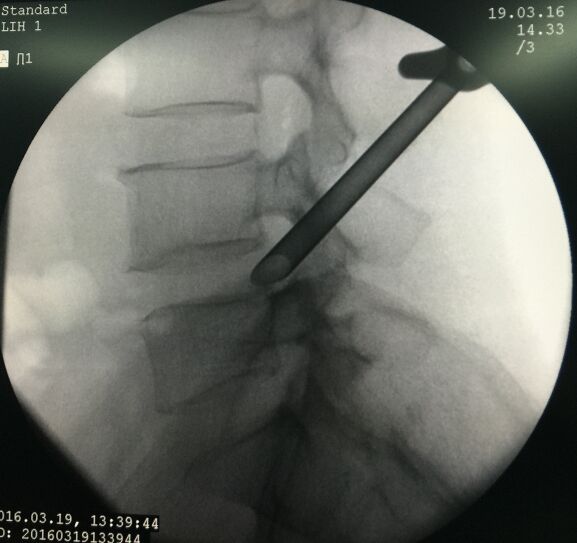

比如家住城关镇的石先生,因4个月前在家里搬煤气瓶后突然出现腰痛及左下肢疼痛,疼痛由左臀部放射到小腿后侧,疼痛剧烈,不能站立及行走,严重影响日常生活。他到处就医,针灸、推拿、中药等各种方法都试了,钱花了不少,腰痛及下肢酸痛麻木丝毫没有改善。3月1日石先生来我院就诊,门诊查体腰椎MRI显示腰椎间盘巨大突出,压迫神经根。董永强主任详细询问病史并通过仔细的检查,决定为石先生实施椎间孔镜下髓核摘除微创手术。

3月4日石老先生在局麻下实施了手术,手术过程顺利,切口十分微小,仅缝了一针。术后仅一天,石先生便可下床活动了。石先生感慨地说:没想到新昌县人民医院有这么好的技术,这么快就解除了我的痛苦,早知道我就不用吃那么多的苦了,感谢人民医院。